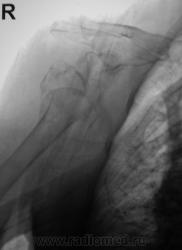

По сравнению со снимками до репозиции определяется гипсовая повязка, в остальном - без динамики

Бесформенность между головкой и впадиной - фрагмент плечевой кости. Репозиция никакая.